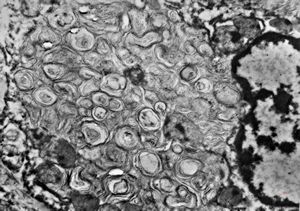

rat | skeletal muscle 6h. post ex. … changes of mitochondrial cristae